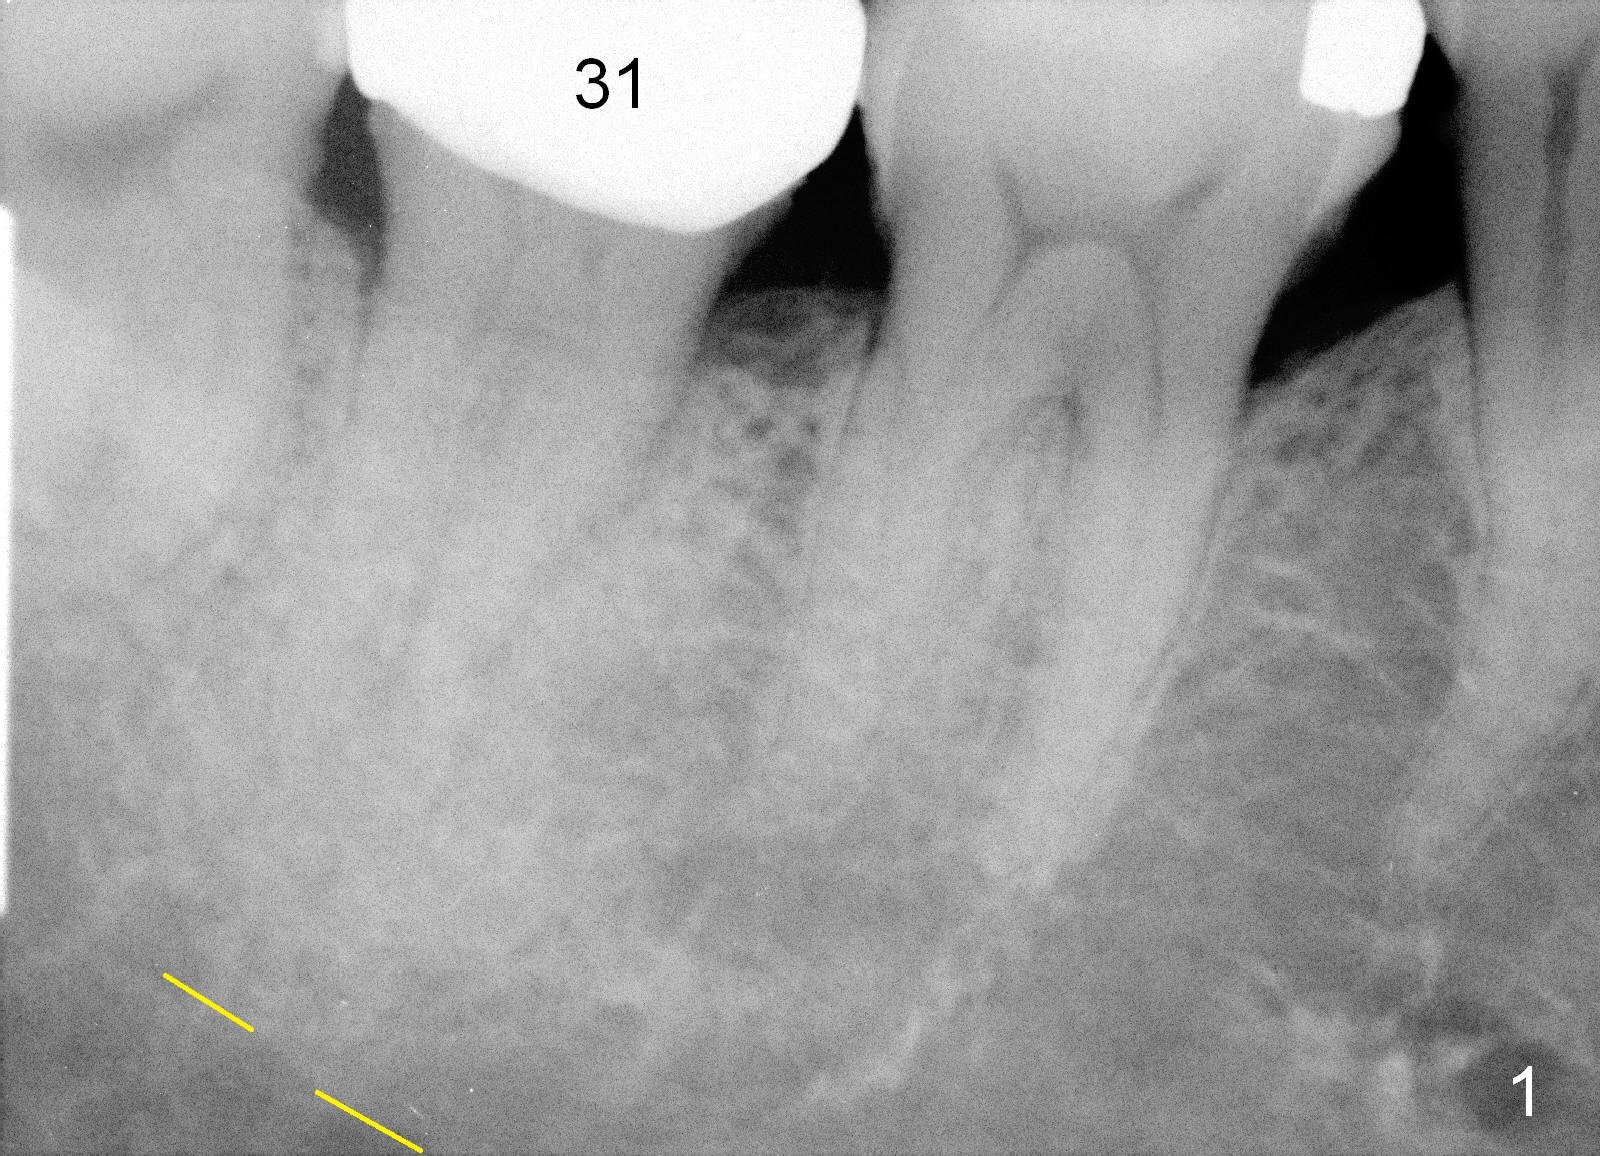

A 69-year-old lady has pain at #31. Because of curved and obliterated root canals (Fig.1,2), it is the better to extract the tooth and have an immediate implant. The roots are also long and narrow and close to the Inferior Alveolar Canal (Fig.1 yellow dashed line), whereas the canal is hardly recognizable in a 2nd PA (Fig.2 ?). For safety, taps are to be used for osteotomy (Fig.3).